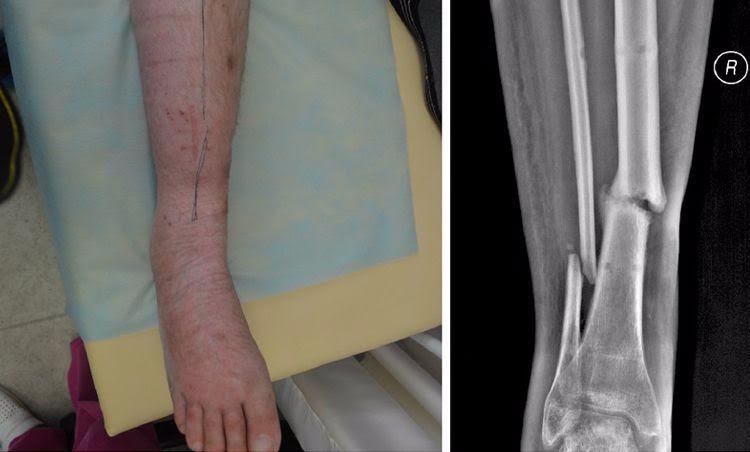

Юрій — боєць 51 ОМБр, травму отримав у липні 2014 року під Слов'янськом. Авто, яким кермував Юрій, підірвалося на ворожому фугасі, осколками тяжко травмувало руку і ногу хлопця. Юрія лікували у трьох шпиталях, та навіть за рік зусиль лікарів кістки гомілки не зрослися.У місці перелому почав формуватися несправжній суглоб, ногу тяжко викрутило — хлопець ледве пересувався навіть на милицях.